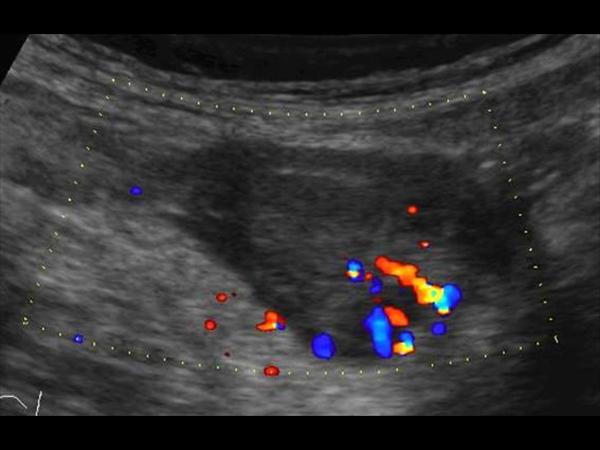

Mucocele ruột thừa

» Thông tin: Nam giới – 71 tuổi.

» Lâm sàng: Đau hố chậu phải mạn tính.